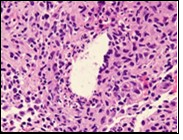

Figure 4.Granulomatous mastitis with epitheloid cell granuloma, langhans and foreign body giant cells with lymphocytic rimming12.

Core needle biopsy of idiopathic granulomatous mastitis enunciates multiple aggregates of non- caseating epitheloid cell granulomas within and encompassing breast lobules, constituted of epitheloid histiocytes, lymphocytes, neutrophils and multinucleated giant cells. Granulomatous inflammation is predominantly lobulo-centric. The inflammation is preponderantly composed of lymphocytes, plasma cells, epitheloid histiocytes, multinucleated giant cells and neutrophils. Neutrophils can configure micro-abscesses and encompass vacant micro-cystic cavities, morphological features which are in common with cystic neutrophilic granulomatous mastitis. Non specific lobulitis along with a lymphoid and plasma cell infiltrate accompanies the granulomatous inflammation. Necrosis is usually absent. Neutrophilic micro-abscesses can be accompanied by fistula formation 4, 5.

Multinucleated giant cells are detected in an estimated three fourths (78.5%) instances. Plasma cells are discernible in around half (53.9%) of the subjects and usually appear at the margins of cystic vacuoles with centric accumulation of neutrophils within the granulomas.